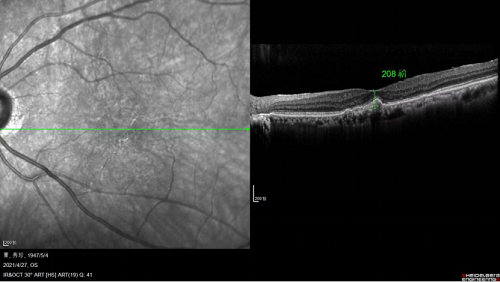

注藥手術(shù)前,黃斑水腫嚴(yán)重

完成一個(gè)療程(三針)治療后

黃斑水腫消退,黃斑厚度大大降低